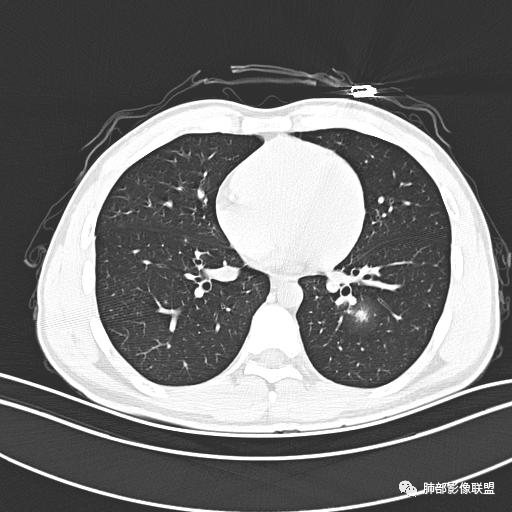

【每日晨读】年轻男性,发热+皮疹+肺内点晕

主  诉:发热、全身皮疹2天。

现病史:患者源于2天前受凉后出现发热,最高体温为38.5℃,且颜面部出现少量皮疹,无鼻塞、流涕、咳嗽、咳痰,未在意而未作特殊处理,次日全身皮疹逐渐增多至全身,伴轻度瘙痒,在当地卫生所给予抗病毒、抗感染治疗(具体用药不详)体温有所下降,但皮疹无明显消退,无腹痛、头痛,食欲无明显减退,为进一步诊治,遂于今日急来我院求治,患者目前精神尚可,体力正常,食欲正常,睡眠正常,体重无明显变化,大便正常,排尿正常。

小强:青年,发热,皮疹;双肺散在结节,周围磨玻璃,点晕征,疱疹病毒感染,鉴别荚膜组织胞浆菌,结核。 大雄:青年,急性起病,发热伴全身皮疹2天,抗病毒治疗体温有下降。双肺随机分布大小不等类圆结节,“点晕征”。考虑水痘-疱疹病毒(VZV)血播询问接触史,查体皮疹分布以及形态基本可诊断。 王开金江津中心医院呼吸科:青年男性,起病急,病程短,以发热,皮疹为首发症状,感染指标以单核细胞升高为主,胸部ct双肺多发结界,周围有晕,点晕表现,随机分布,同意於老师意见,水痘疱疹病毒血流感染累及肺。 王秀仙:双肺多发大小不等结节,周围有晕,边缘模糊,呈点晕征表现。青年,急性起病,发热伴全身皮疹2天,抗病毒治疗体温有下降。考虑疱疹病毒。鉴别荚膜组织胞浆菌。 傅昌瑜:19岁男性,发热、全身皮疹2天,单核细胞增高,双肺多发结节,结节边缘见边界不清磨玻璃影。点晕征+发热、全身皮疹+单核细胞增高——考虑水痘-带状疱疹病毒肺炎。 一切∮随缘:年轻男性,发热,皮疹两天,实验室,CRP,PCT增高,影像:双肺多发散在磨玻璃结节,边界欠清,大小不等,呈点晕征改变,以血管束周围分布为主,局部血管束略增粗,其它无明显改变,考虑:1:病毒性肺炎(水痘疱疹病毒?不知道皮肤有无改变)2:真菌(组织胞浆菌,血管侵袭性肺曲霉)3:GPA4:寄生虫(实验室没有看到嗜酸细胞增高) 赵山河:双肺散在结节,周围有晕,边缘模糊,呈点晕征表现。青年,急性起病,发热伴全身皮疹2天,抗病毒治疗体温有下降。考虑水痘—疱疹病毒感染。洪桥爱:青年男性,发热、皮疹2天,伴瘙痒,皮疹于面部首发,之后进展至全身,虽然没有对皮疹进行描述,但是从出疹时间及皮疹进展情况,伴瘙痒,应该就是个水痘患者;CT提示双肺随机分布结节影,部分结节伴有边界不清晕征,考虑水痘血播肺。 刘强:年轻男性,急性起病,皮疹,发热,抗感染治疗体温下降,说明有效。影像表现为散在点晕征,感染类疾病谱(疱疹病毒,真菌,结核),结合年龄,皮肤皮疹,考虑水痘-疱疹病毒性肺炎。 小兜:男性,19岁,发热皮疹两天,颜面部至全身,CRP,降钙素及单核增高。CT示双肺散在小结节,周围伴磨玻璃影,点晕征,考虑为水痘-带状疱疹病毒(varicella-zoster virus,VZV)肺炎 必有路:青年,皮疹+发热+“点晕征”→水痘-疱疹病毒(VZV) 许慧良:青年男性患者,发热、皮疹2天,体温最高38.5℃,第3天皮疹扩展至全身,伴瘙痒,胸部CT:双肺多发随机分布的小结节,结节周边见边界模糊的晕征,考虑水痘病毒感染流心明智:男,19,急性起病,发热伴全身皮疹2天。出疹顺序头→全身,抗病毒有效。胸部CT:两肺多发大小不等类圆形实性小结节影,随机分布,结节周围环绕GGO,边界模糊,呈点晕征。出疹特点是关键,未提示。考虑:血播病毒性肺炎,水痘-疱疹病毒?麻疹?鉴别荚膜组织胞浆菌、TB、血管炎、寄生虫等。 浪迹天涯:病灶多为5-10mm大小结节,结节周围可见磨玻璃样的晕环,常多发,可分布于肺内任何区域,考虑水痘—带状疱疹病肺炎如果短时间内有新的一个区域浸润,更加能说明,